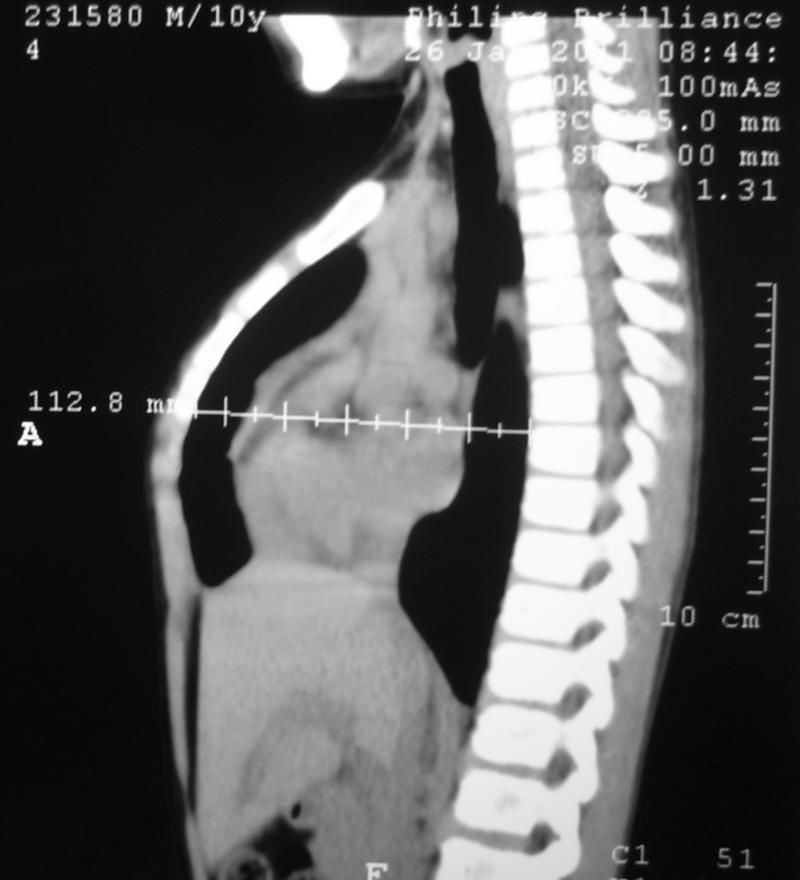

CASO 2: Hombre 10 años de edad.

Corrección quirúrgica. Operación de Abramson.

Se implantó barra metalica de compresión interna con fijación costal bilateral.